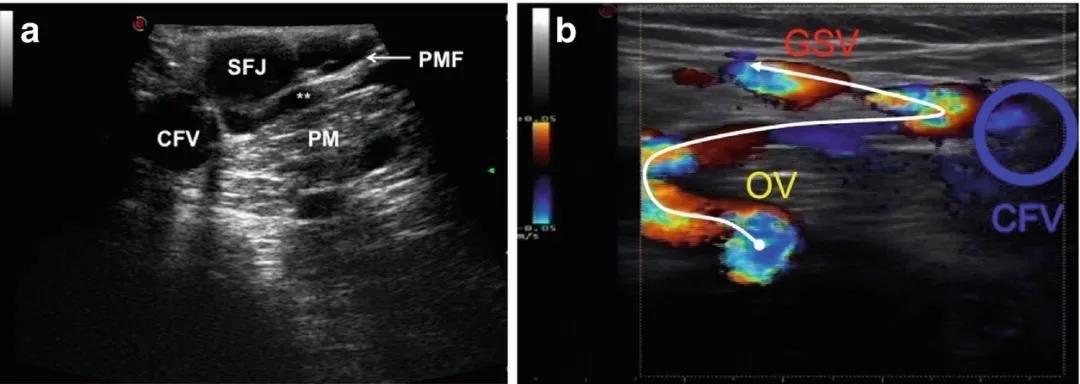

静脉分流通路(Venous Shunt,简称Shunt)是指静脉血流的反常通路。一个Shunt一般携带有两种血流,引流(Drainage)血流以及分流(Shunt)血流。分流通路的重要性依赖于它的分流血流,分流的起始点以及终结点。起始点被称之为反流点(EP),终结点被称之为回流点(RP,通常是回流的穿静脉)。

在所有分型中,SHUNT3(或SHUNT III)是最常见的,有学者统计占据60%的下肢静脉曲张人群。

SHUNT3的特点是:

- N1-N2-N3-(N2)-N1反流

- N2上没有超声可探及的回流点存在

- 1个闭环式分流通路同时行经3个静脉网